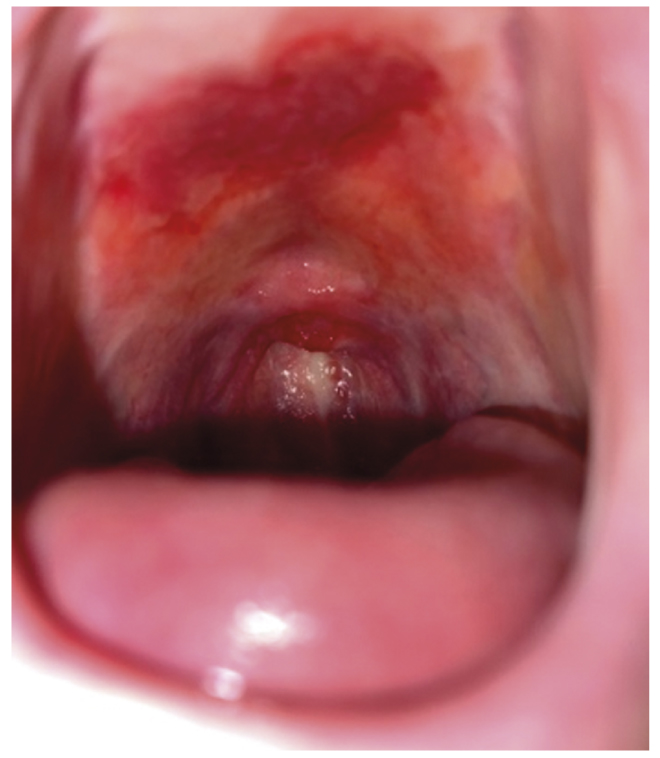

The physical status of the patient corresponded to class II–III of the scale by the American Society of Anesthesiologists (ASA). The surgical intervention, by its extent and type, was considered as the surgery with moderate traumatic degree. Preoperative evaluation of the status of the upper airways has revealed the risk factors of difficult mask ventilation according to the MMMMASK scale (Mask seal due to the absence of teeth; Mallampati — class IV), difficult installation of the supraglottic air tube according to the RODS scale (R — limited opening of the mouth) and difficult direct laryngoscopy. The criteria for difficult airways were also determined: mouth opening — 2.9 cm (microstomia) (Fig. 1), large tongue, complete edentia, thyromental distance — 6 cm, sternomental distance — 9 cm, hyomental distance — 4.5 cm, Mallampati test — IV (Fig. 2), presence of chronic erosions in the oral cavity (Fig. 3).

Fig. 3. Chronic erosion of the hard palate.